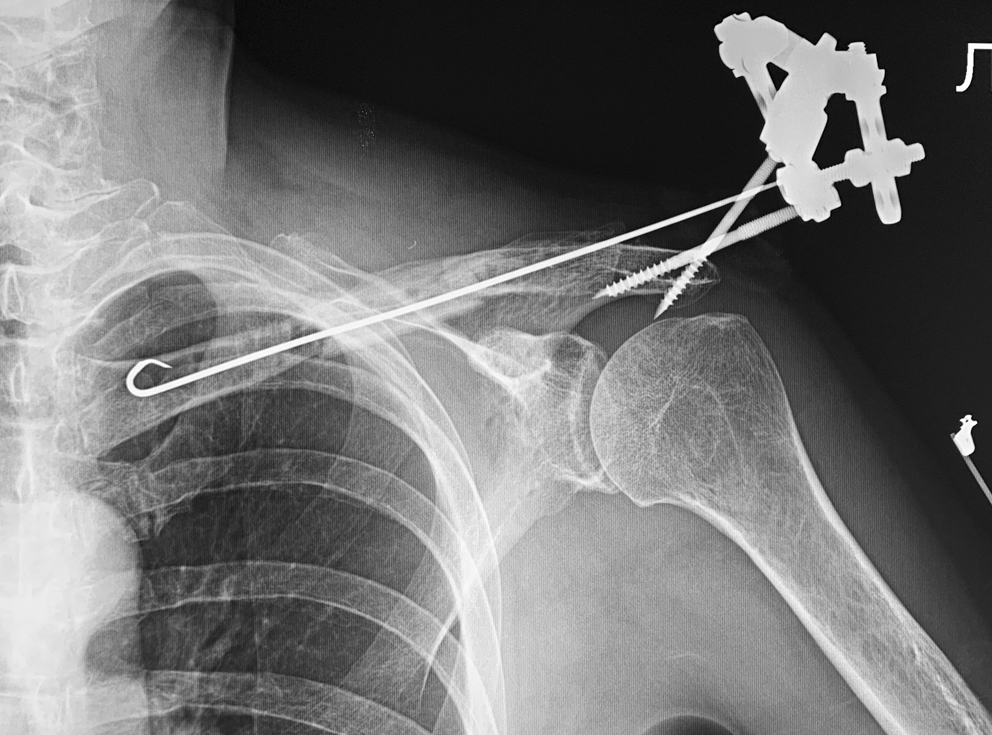

Преследуя эту цель, 21.05.2021 г. под наркозом мы удалили пластину из доступа по старому послеоперационному рубцу, причем сигнальный лоскут кожи с учетом топографии сосудистого анастомоза обошли сверху. Затем, освежив концы отломков псевдоартроза и максимально репонировав их ad oculus, со стороны акромиального конца в ключицу по ее длиннику провели спицу диаметром 2 мм, конец которой перфорировал кортикальный слой проксимального отломка и кожу вблизи грудино-ключичного сочленения. Из небольшого разреза мягких тканей над ним осуществлен загиб короткого свободного перовидно заточенного конца на 270° с погружением острия в ткань ключицы. Таким образом был создан «якорь» на проксимальном отломке для последующей компрессии на стыке его с трансплантатом. Свободный конец спицы со стороны акромиального конца кости зафиксировали в стержне-«тягуне» аппарата Илизарова, который смонтировали к опорной системе. Последняя представляла собой консольную планку на 4 отверстия из комплекта аппарата, фиксированную на двух самонарезных стержнях, введенных в акромиальный отломок. Такая компоновка за счет тяги спицы к акромиальной опоре позволила создать компрессию на стыке отломков ключицы на операционном столе и поддерживать ее в последующем (рис. 7).

Рис. 7. Рентгенограмма после КНО ключицы

Через 4,5 мес. возникло воспаление тканей у стержней акромиальной опоры с потерей стабильности фиксации, в связи с чем опора была демонтирована, а спица «перекушена» над кожей (рис. 8 а). После дообследования дистальный конец спицы под внутривенным наркозом из небольшого разреза был погружен в акромиальный конец ключицы, таким образом спица осталась армирующим элементом обеих зон сращения. После заживления раны первичным натяжением пациент приступил к комплексной реабилитации, включающей пассивно-активную ЛФК и ФТЛ по индивидуальной программе.

При осмотре через 4 мес. после выписки из стационара пациент жалоб не предъявлял, мог выполнять бытовую деятельность в полном объеме. Объем движений в плечевом суставе возрос: отведение — 85°, передняя девиация — 90°, задняя — 45° по В.О. Марксу. Мышечная сила движений составляла 3,5–4 баллов. Рентгенологически сращение подтверждено, увеличилась плотность костного регенерата в зоне сращения (рис. 8 b).

Рис. 8. Рентгенограммы ключицы после демонтажа акромиальной опоры (а) и окончательного этапа лечения (b)